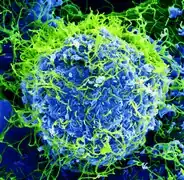

Selected image –

Photo credit: Public domain (U.S. Brookhaven National Laboratory)